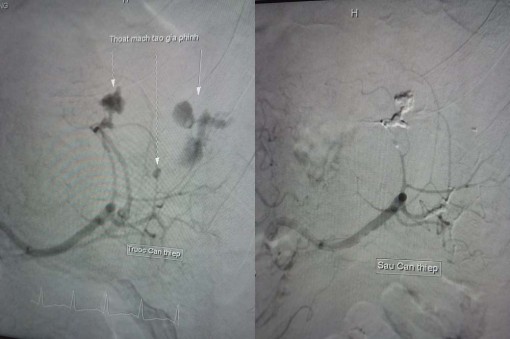

Nam bệnh nhân 35 tuổi bị tai nạn giao thông vỡ lá lách độ 3, đang chảy máu bụng được các bác sĩ điều trị thành công mà không cần phẫu thuật.